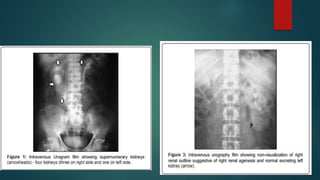

Horseshoe kidney

Supernumerary kidney

• #38 Pancake kidney (also known as discoid kidney, disc kidney, lump kidney, fused pelvic kidney or cake kidney) is a rare renal fusion anomaly of the kidneys of the crossed fused variety.